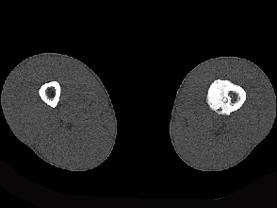

问题 患者,男,23岁,左大腿远端疼痛,夜间明显,服阿司匹林可缓解,请结合所提供图像,选择最佳答案 ( )

选项 A、骨巨细胞瘤 B、骨肉瘤 C、骨样骨瘤 D、骨化性纤维瘤 E、骨脓肿

答案 C